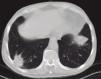

For the last 8 months, the patient had had a dry cough, accompanied by asthenia, anorexia and a weight loss of 6 kilograms. In view of the constitutional syndrome with cough, outpatient investigations had been undertaken, showing an initial creatinine level of 3.5mg/dL, which increased to 4.9mg/dL 10 days later. Renal ultrasound revealed normalsized kidneys with correct corticomedullary differentiation, and a thoracic CT scan showed lesions compatible with two pulmonary masses. One was located in the anterobasal segment of the left lower lobe (LLL) and measured approximately 5 × 4cm. The other was located in the posterobasal segment of the right lower lobe (RLL), measured approximately 4 × 3cm, had poorly-defined edges, and an air bronchogram in its interior. There was also slight peripheral infiltrate in the apical region of the RLL, with a non-specific inflammatory appearance. Another finding of note was the presence of mediastinal lymphadenopathies. A bronchoscopy was then performed, showing moderate infiltration of the subsegmental spur of the right basal segment, which was biopsied. Bronchial aspirate samples were taken for microbiology and cytology. Ziehl-Neelsen staining was negative. An attempt to perform a fine-needle aspiration biopsy of one of the pulmonary masses was unsuccessful due to technical problems; therefore, an in-patient mediastinoscopy was arranged with the Thoracic Surgery Department.

The protein analysis showed beta-gamma bridging. The bone marrow aspirate ruled out monoclonal gammopathies. We repeated the thoracic CT scan and confirmed the previously described pulmonary nodular images and mediastinal lymphadenopathies. The thoracic surgeons performed a mediastinoscopy with lymph node biopsy; lymphomatous disease was ruled out in the histology report.